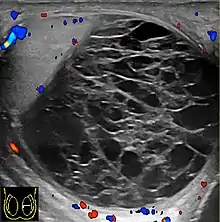

Fibrotic striations

A striated pattern of the testicle, radiating from its mediastinum, does not have clinical importance unless there are alarming symptoms or abnormal signal on Doppler ultrasonography.[6] It is presumed to represent fibrosis.[6]